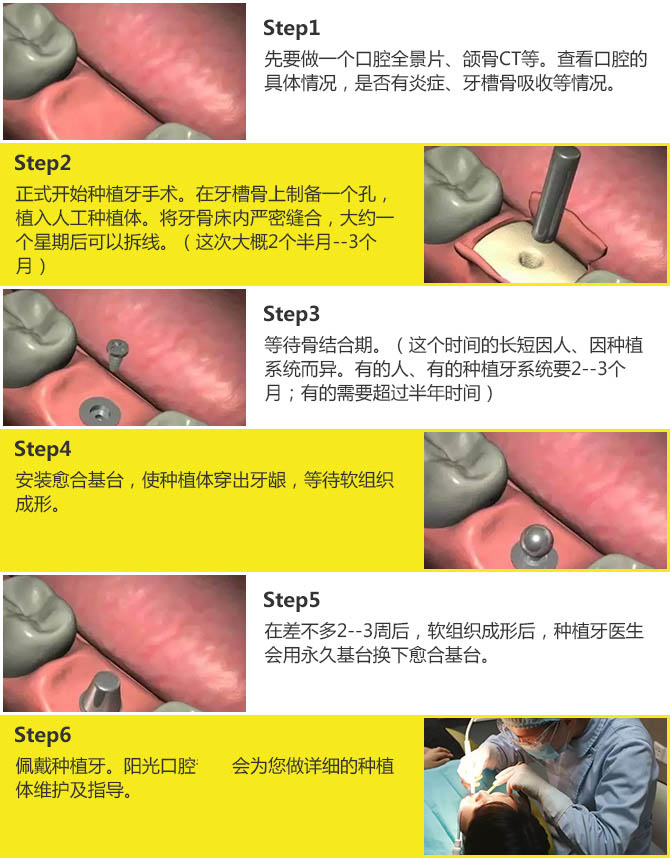

6步科学种植流程,种出健康好牙